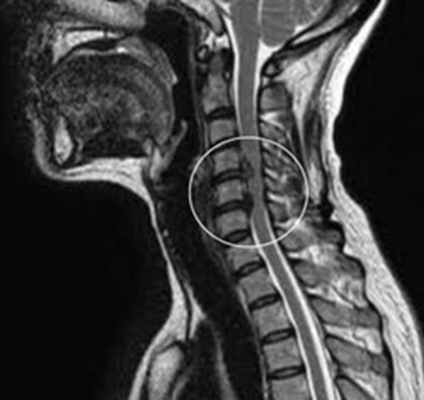

Диагноз подтверждается результатами магнитно-резонансной или компьютерной томографии.

Магнитно-резонансная томография или компьютерная томография

Диагноз может быть подтвержден с помощью магнитно-резонансной (МРТ) томографии или миелографии Миелография Для подтверждения диагноза, предполагаемого на основании медицинского анамнеза и неврологического обследования, может понадобиться выполнение диагностических процедур. Электроэнцефалография. Прочитайте дополнительные сведенияЛечение

- МРТ-сканирование, которое создает изображения с использованием радиоволн и магнитного поля, помогает врачу обнаружить компрессию нервных структур.

Диагноз цервикального спондилеза устанавливают на основании МРТ, КТ или КТ-миелографии.

Диагностика проводится при помощи МРТ или КТ.